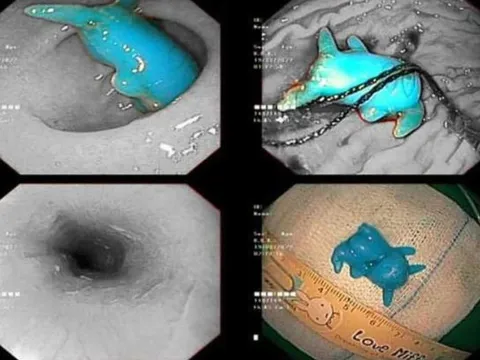

Nghệ An: Lấy viên sỏi san hô “khủng” từ bụng người đàn ông 58 tuổi

Vừa qua, các bác sĩ bệnh viện Đại học Y khoa Vinh (Nghệ An) đã phẫu thuật và lấy thành công một viên sỏi san hô “khủng” từ cơ thể một bệnh nhân.